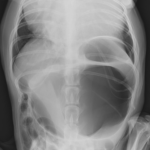

高齢(12歳)のアフガンハウンドが吐きたそうだけど、何も出てこない。次第に起立出来なくなったとのことで夜間に救急で来院しました。症状とエックス線検査から胃捻転と診断しました。また聴診時に心音は遠く、聴取出来ませんでした。胸部エックス線検査においてムーンハートが確認されました。超音波ガイドで出血性心のう水を2リットル抜去しました。バイタルサインが落ち着いたところで胃捻転整復術を実施しました。その後も出血性心のう水は貯留傾向にありました。高齢であることから血管肉腫が疑われましたが、各種画像診断においても腫瘤の存在はなくまた細胞診においても血管肉腫の可能性は低いものと判断しました。胃捻転から2週間後、心膜の生検と再発性の心膜貯留を回避する目的で心膜切除術を実施しました。心膜は顕著に肥厚し、線維化を伴っていました。病理検査の結果をもとに内科療法を併用する予定です。高齢ながら頑張ってくれました。